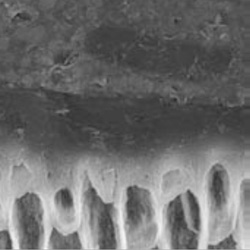

Cuando aplicamos grabado ácido total en la dentina, se retira la parte inorgánica, desmineralizándola, dejando un aspecto de red, aunque los túbulos dentinarios se siguen observando. De esta manera, quedaría sólo la materia orgánica compuesta de colágeno, pues éste no se ve afectado por el ácido ortofosfórico. Puedes observar en las siguientes imágenes las estructuras antes y luego de la aplicación del ácido.

Fuente: © M. Nordvi, UiO, 2002-2003

Pashley DH et al. Dent Mater 2011; 27: 1-16.